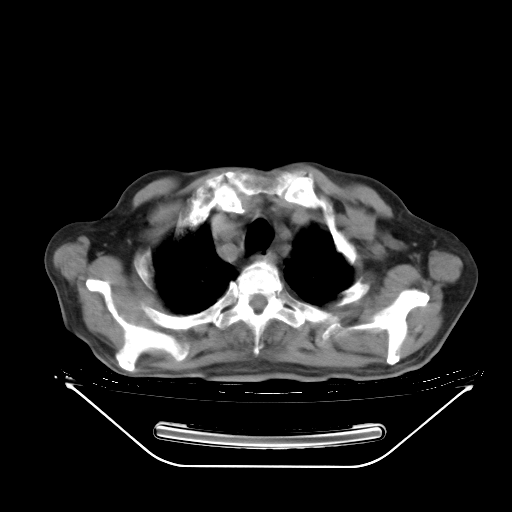

今天复查肺部CT,发现双肺广泛磨玻璃样改变。所以我把3月19日和5月9日相隔50天的肺部CT上传。请大家会诊。

2009年3月19日肺部CT片。

5月9日肺部CT(在4月27日齐鲁医院肺部CT描述部分肺组织磨玻璃样改变,12天后肺组织广泛磨玻璃样改变)

大致读了系列胸部CT:纵隔窗无明显异常,肺窗:从4、27至今:主要是双肺中下野外带可见毛玻璃样改变,目前处于急性肺泡炎阶段,至于原因考虑1、结替组织或胶原血管性疾病所致?2、恶性疾病如恶组在肺部所致的表现或细支气管肺泡癌?3、药物或其它原因如肺蛋白沉着症所致肺泡炎目前不太可能?总之,明天就去请我院的呼吸科、感染科、血液科和临免专家会诊哈。